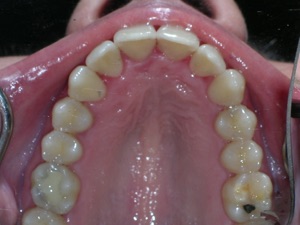

This case was of a young lady who desperately wanted Invisalign, but had been told it was not possible. There was not one, but two teeth that had come in toward the roof of the mouth.

Now for the final results.

Needless to say, we were both quite happy with the outcome. Using elastics we were able to push back the back teeth and create space for the two teeth stuck behind.